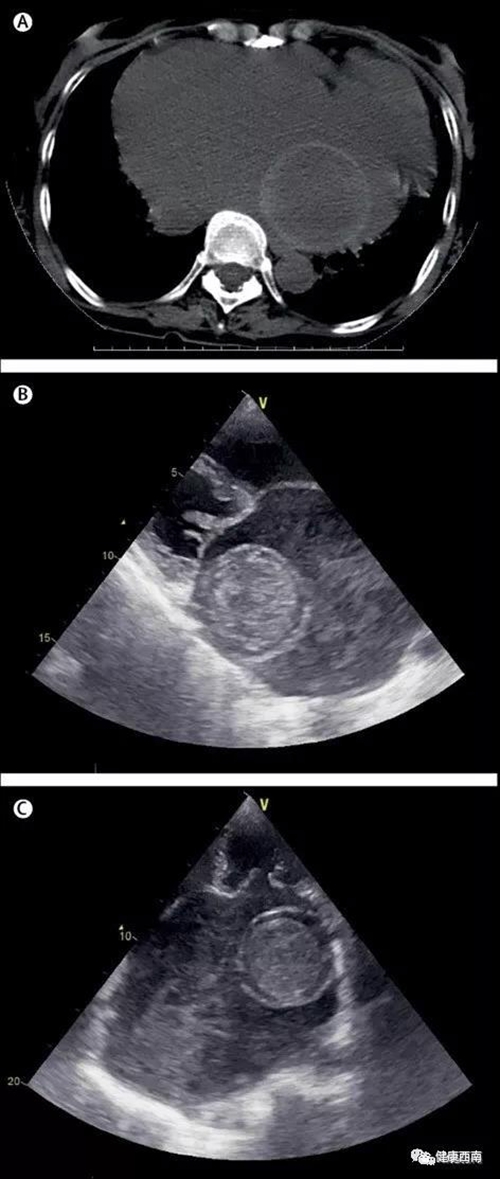

西南医科大学附属医院首次在《柳叶刀》上发表的文章,是围绕一例患有风湿性心脏病病史妇女的的病例:其CT扫描和经胸超声心动图可见其左心房有一个“同心圆”,并就此开展诊断与治疗。作者为西南医科大学附属医院的医生夫妻:36岁的心脏大血管外科医师谢小均和31岁的影像科医师白娇。

2018年1月,一位51岁的妇女因意识下降和偏瘫住进西南医科大学附属医院心脏大血管外科。患者有风湿性心脏病的病史,经初步神经检查符合右侧偏瘫。她的头部CT扫描证实了左侧基底节和左室旁脑区的脑梗死。胸部CT扫描显示左心房有直径为6cm,呈边缘高密度的同心圆形。进一步的经胸超声心动图检查显示,左心房肿块亦有“同心圆”。随后的病理检查证实这是一个巨大的血栓,外壳光滑,表面以下有多个出血区。这可能是CT扫描和经胸超声心动图所见“同心圆”的原因。左房球血栓几乎总是形成于二尖瓣疾病的背景下,并与高栓塞率有关。及时手术切除是推荐和适当的治疗措施。